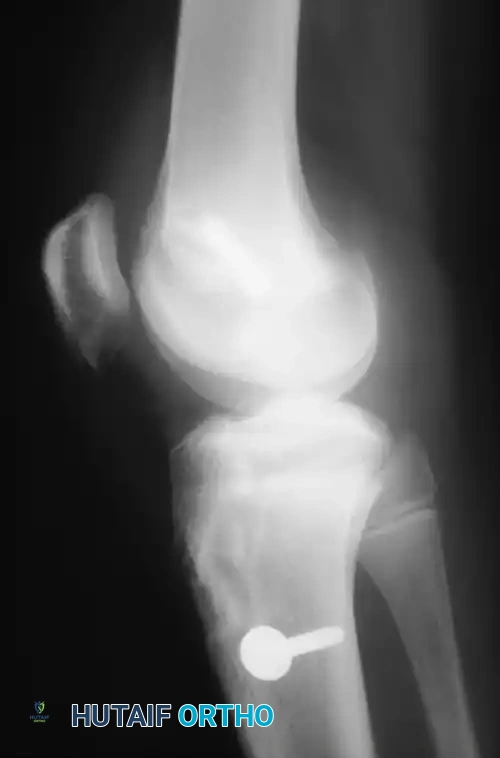

Radiographs:

Standard weight-bearing orthogonal views are mandatory. While often normal, specific radiographic signs are highly indicative of ACL injury:

* Segond Fracture: An avulsion fracture of the anterolateral tibial capsule. This finding is considered pathognomonic for an ACL tear.

Image

Fig. 43-101 Avulsion fracture of the tibia (Segond fracture) with anterior cruciate ligament tear.